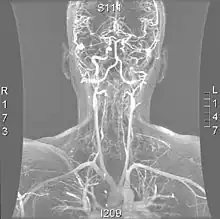

| Cerebral Angiogram obtained using an iodine based contrast medium | |

Cerebral atherosclerosis is a type of atherosclerosis where build-up of plaque in the blood vessels of the brain occurs. Some of the main components of the plaques are connective tissue, extracellular matrix, including collagen, proteoglycans, fibronectin, and elastic fibers; crystalline cholesterol, cholesteryl esters, and phospholipids; cells such as monocyte derived macrophages, T-lymphocytes, and smooth muscle cells.[1] The plaque that builds up can lead to further complications such as stroke, as the plaque disrupts blood flow within the intracranial arterioles. This causes the downstream sections of the brain that would normally be supplied by the blocked artery to suffer from ischemia.[2] Diagnosis of the disease is normally done through imaging technology such as angiograms or magnetic resonance imaging. The risk of cerebral atherosclerosis and its associated diseases appears to increase with increasing age;[3] however there are numerous factors that can be controlled in attempt to lessen risk.[4]